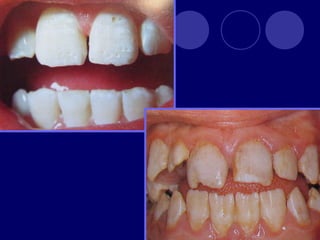

ANOMALÍAS DEL COLOR

 PIGMENTACIÓN

POR

TETRACICLINA:

 Gris marrón, amarillo

 ERITROBLASTOSIS

FETAL:

 Amarillo verdosa

ANOMALÍAS DEL COLOR PIGMENTACIÓN POR TETRACICLINA:  Gris marrón, amarillo  ERITROBLASTOSIS FETAL:  Amarillo verdosa